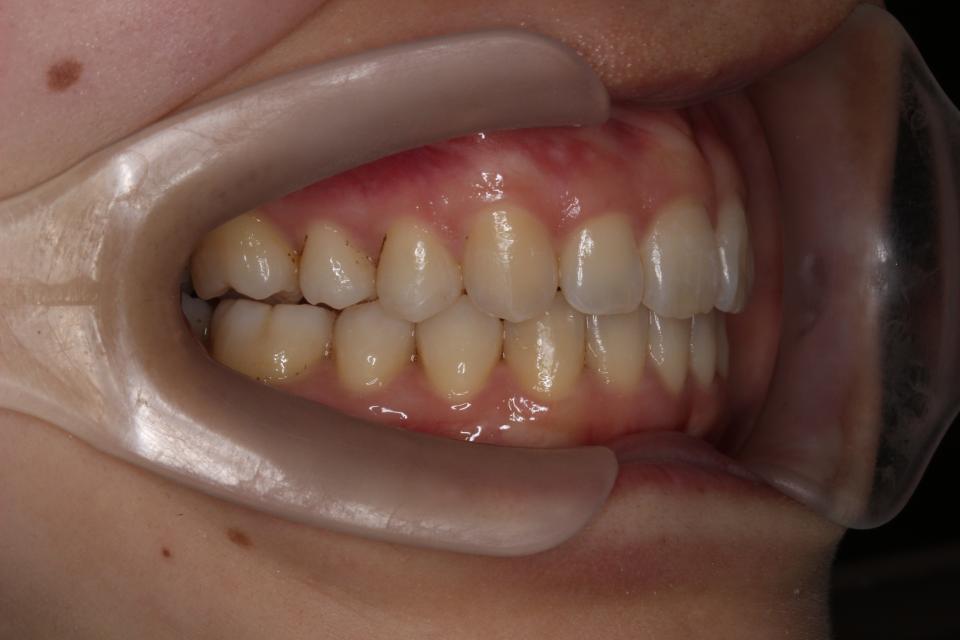

上顎前突(出っ歯)のマウスピース矯正治療例(抜歯あり)

矯正治療前

矯正治療後

20代女性の患者さんです。

歯並びのガタガタと出っ歯気になり矯正治療を始めました。

左上4番目の歯を抜歯して、マウスピース型の矯正治療装置を使用し、歯のやすり掛け(IPR)を行いました。